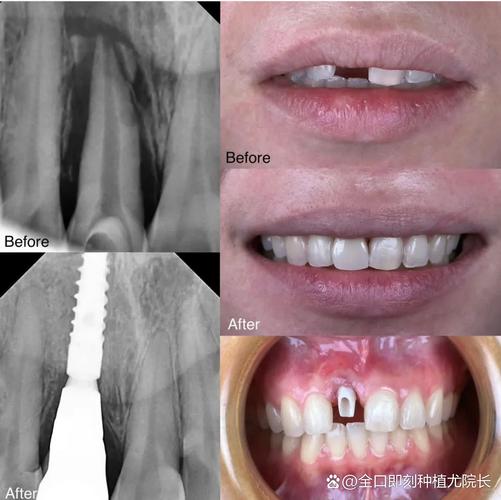

上颌种植8颗通常采用“All-on-8”技术,通过前牙区与后牙区种植体的合理分布,兼顾美学与力学支撑,种植体位置需避开上颌窦、颏孔等重要解剖结构,同时确保咬合力均匀分散。

- 即刻负重与延期负重:若患者骨条件好、初期稳定性高(种植体植入后扭力>35N·cm),可考虑即刻负重(当天戴临时牙冠);否则需延期3-6个月,待骨结合完成后戴牙。